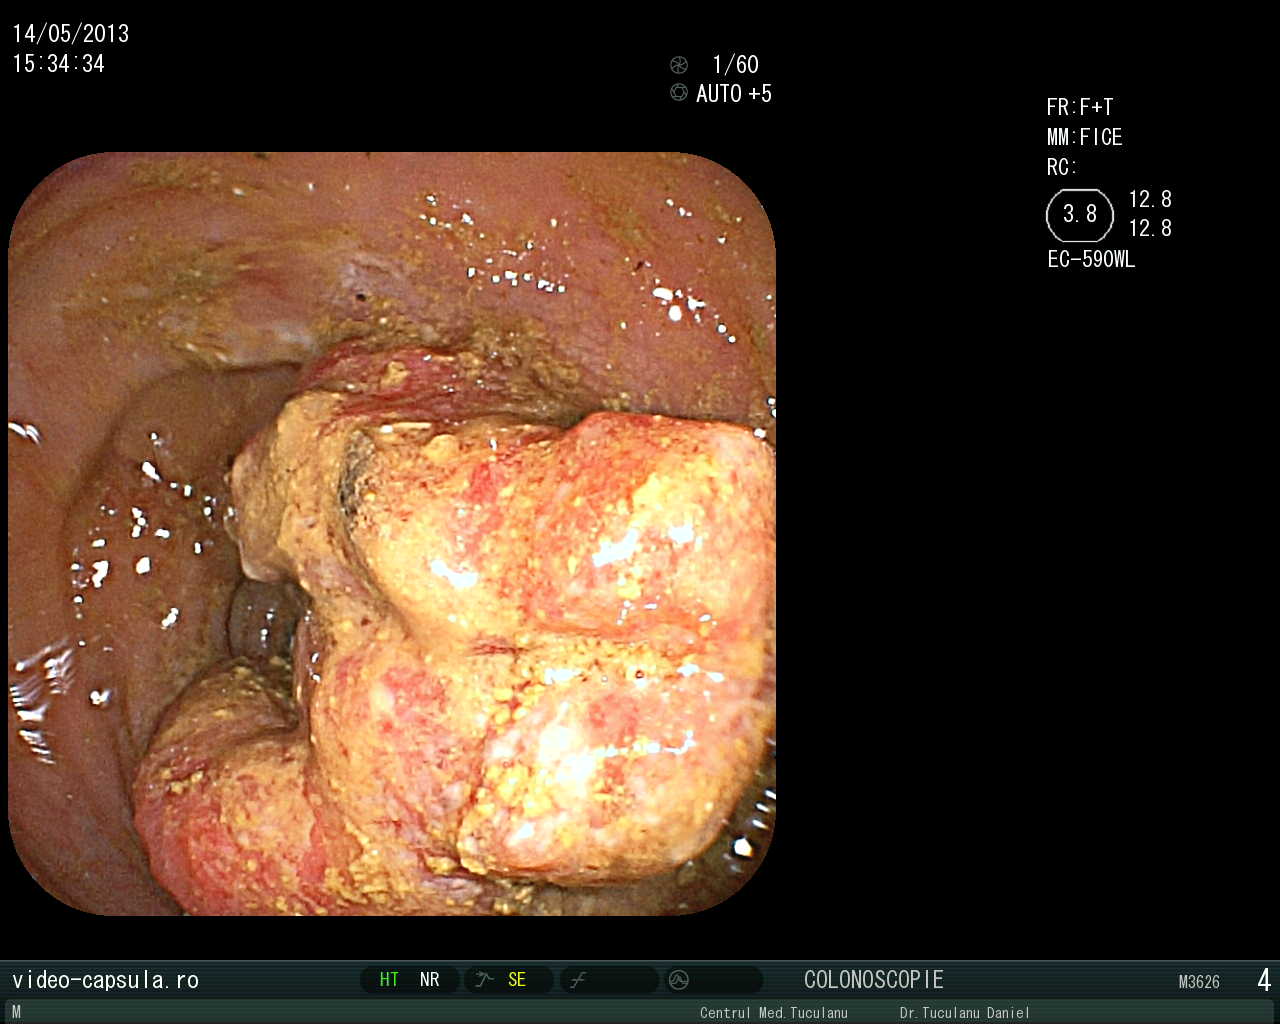

• Stent în cancer sigmoidian inoperabil •

Tratament endoscopic (nechirurgical) pentru evitarea operației paleative sau anusului contra naturii în cancerul colo-rectal avansat

Depistarea precoce a cancerului colo-rectal, formă tot mai frecventă de cancer